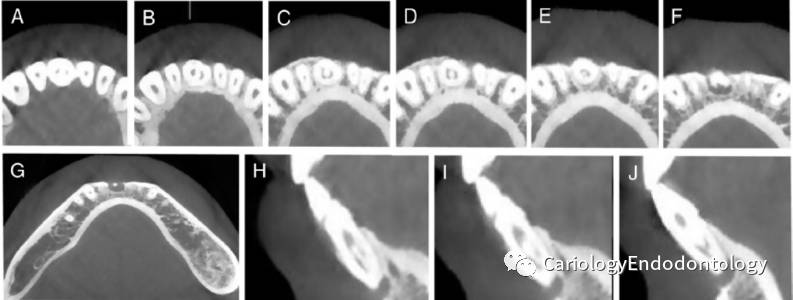

4CBCT检查:

1)牙内陷从冠方延伸到根管根尖区;

2)从近中颈部(唇侧和舌侧)到牙根中部(唇侧),然后到达根尖区(舌侧);

3)根尖周透射区大约6.5X7.8X8.0mm,颊侧骨板不连续;

4CBCT矢状位显示:根管被牙内陷结构分开,形成一个宽的近中腔,和一个环形的远中腔。见图2 A-J